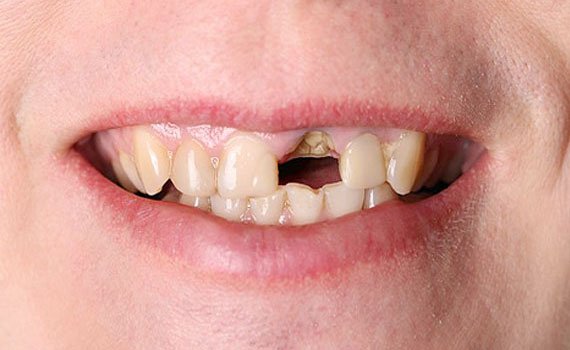

Welcome to Care 32 Dental Clinic & Implant Center, your trusted destination for comprehensive dental care. Located in the heart of the city, we specialize in providing a wide range of dental treatments to ensure the health and beauty of your smile. Our clinic offers advanced technology, a professional team of experts, and a comfortable environment to make your visit stress-free and effective. Whether you're in need of a routine check-up or complex dental procedures, we provide the highest standards of care with personalized attention to meet your needs.